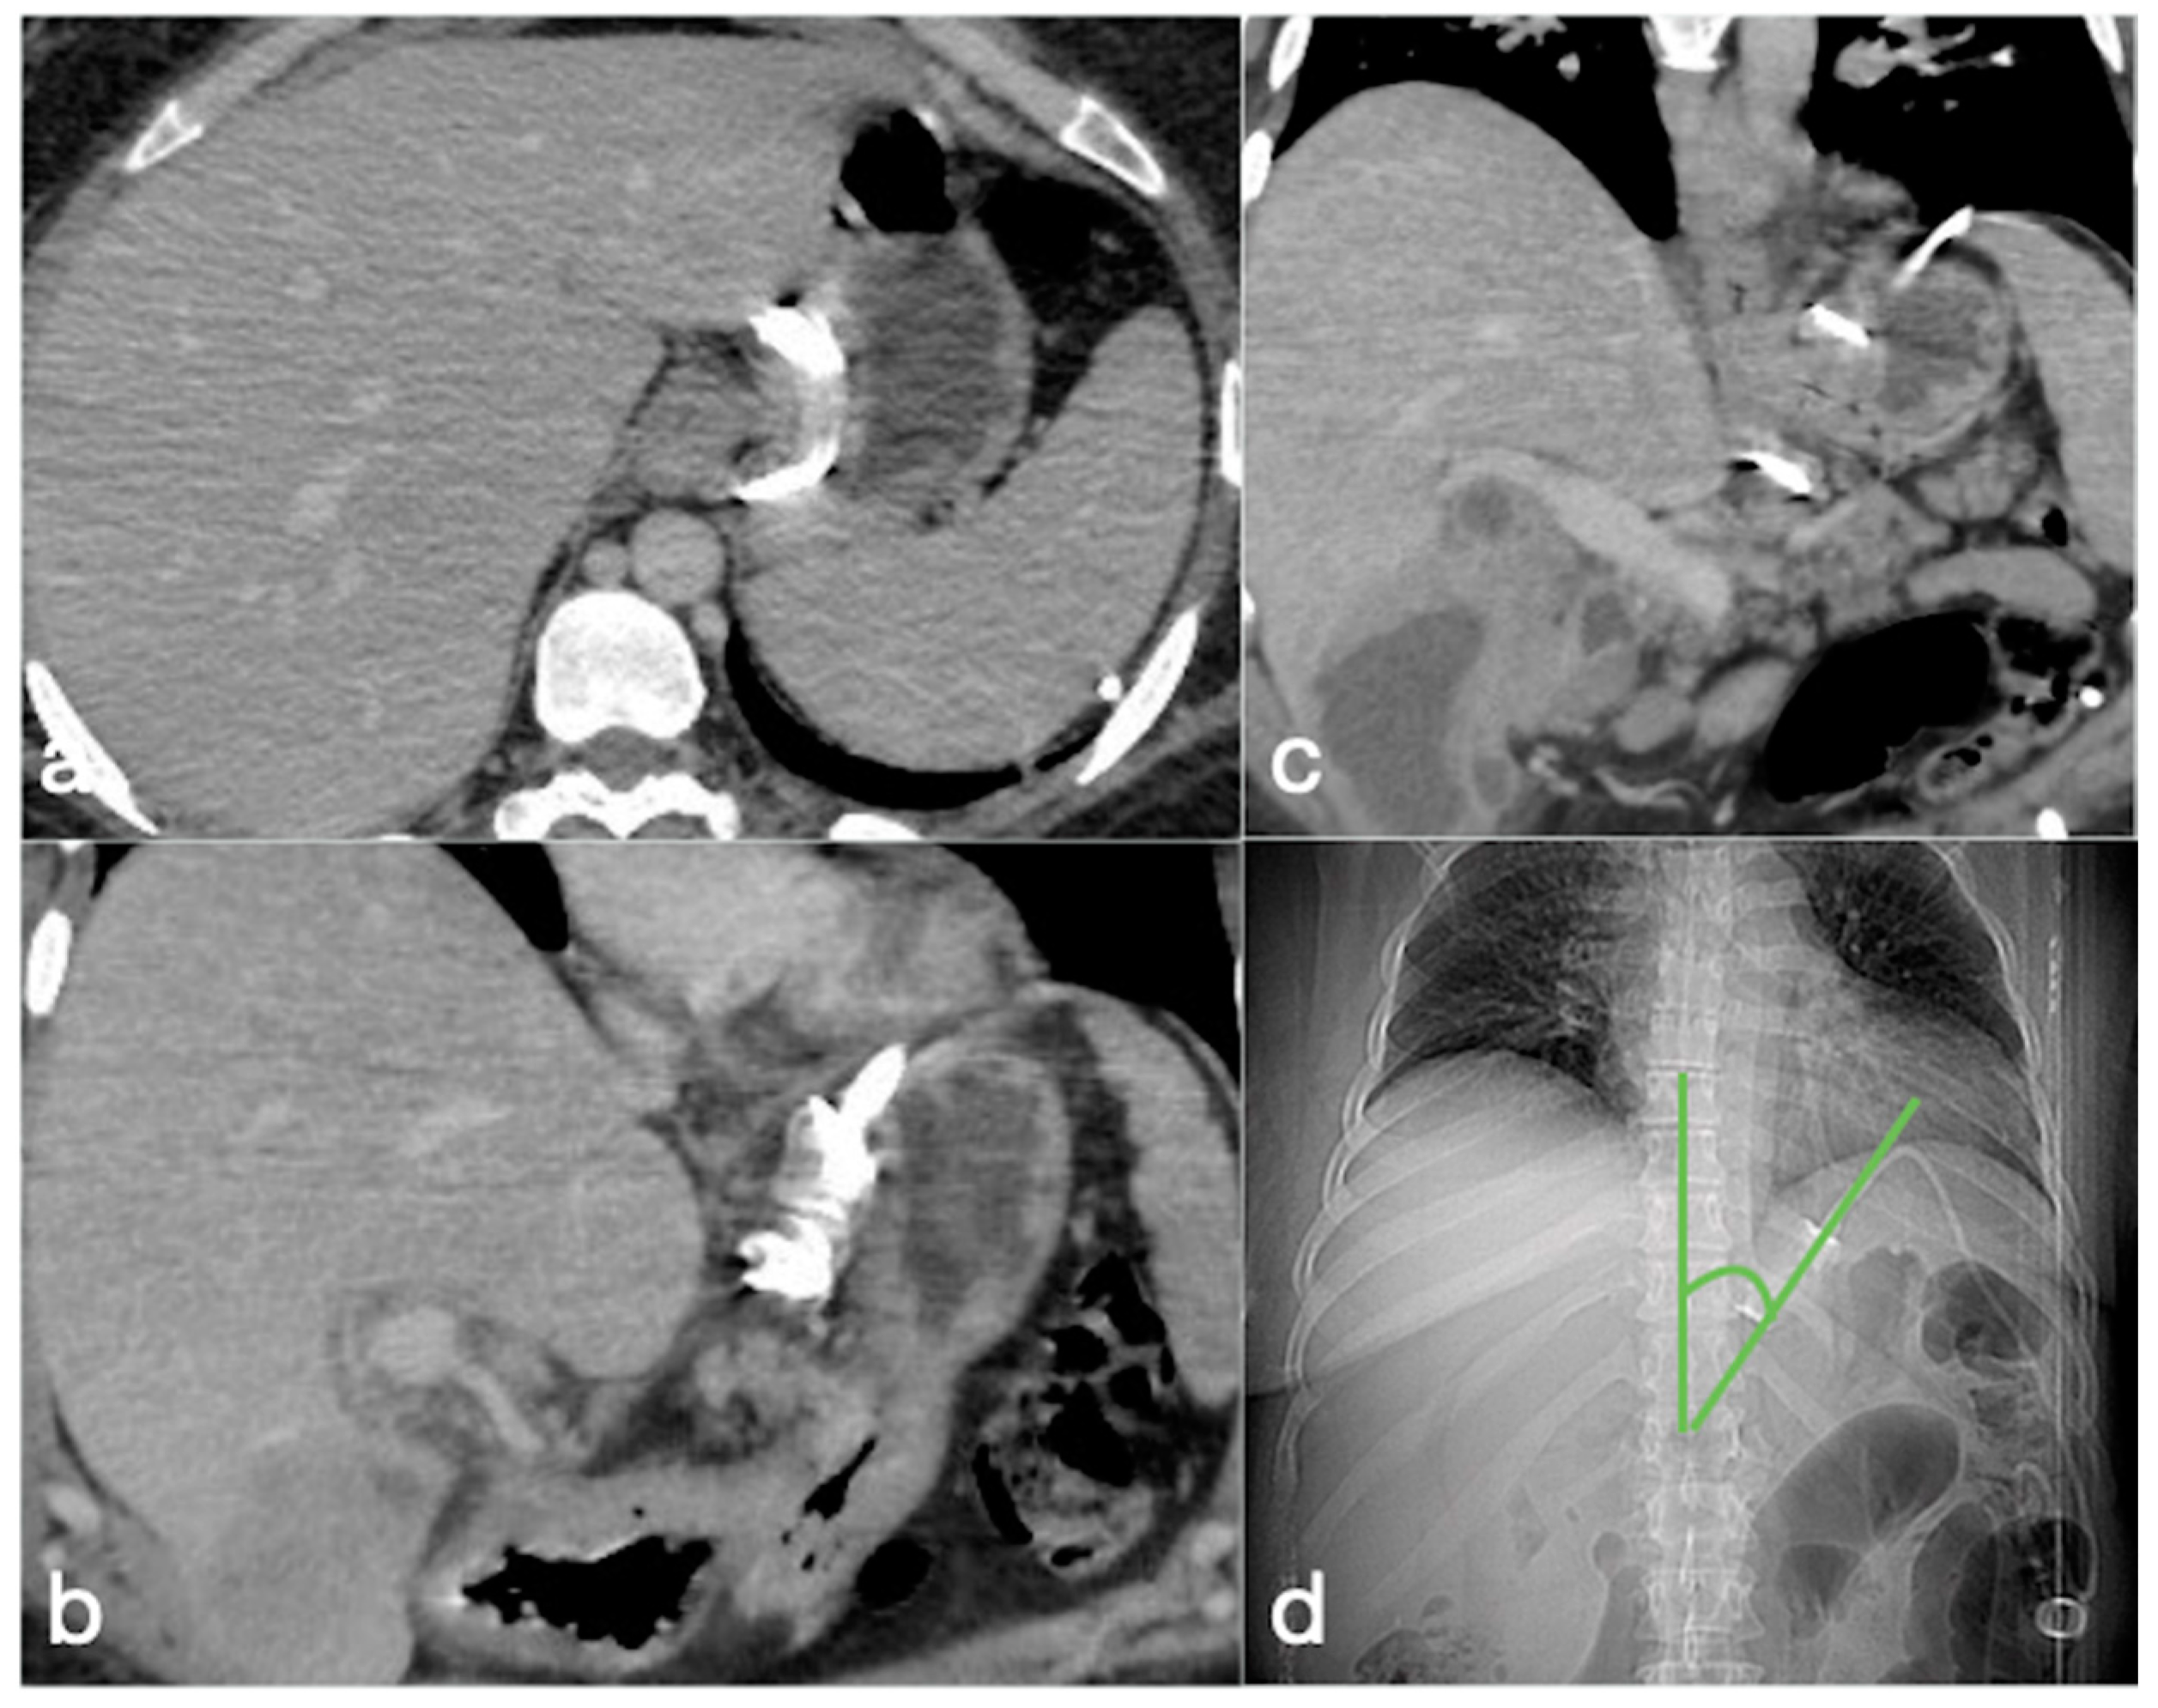

Figure 8. Gastric outlet obstruction. A 28-year-old female patient with a gastric balloon came to the emergency department complaining of sudden abdominal pain followed by persistent vomiting. Note the stomach overdistension proximal to the balloon, displaced in the antro-pyloric region (ac, axial views, d, coronal view; balloon, arrows).